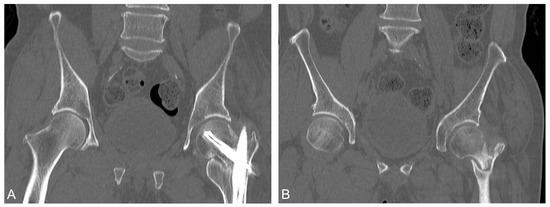

Teriparatide as an Effective Nonsurgical Treatment for a Patient with Basicervical Peritrochanteric Fracture Nonunion—A Case Report

The nonunion rate of surgically treated basicervical peritrochanteric fractures has been reported to be as high as 9%. Due to the high 1-year mortality rate following revision surgery, finding an effective nonsurgical treatment option is of interest. Over the last decade, numerous reports have been published that have suggested teriparatide as an effective treatment for certain types of fracture nonunion. However, the literature focused on teriparatide treatment for proximal femoral fracture nonunion is scanty. A 70-year-old man suffering from a left hip basicervical peritrochanteric fracture received cephalomedullary nail fixation. Nine months after the surgery, the patient still complained of left hip pain referring to the medial thigh with an antalgic limping gait. No sign of healing was noted for more than a consecutive 3 months of follow-up. Fracture nonunion was diagnosed and further confirmed by the computed tomography (CT). The patient preferred nonsurgical treatment after thorough discussion. He then received 4 months of subcutaneous teriparatide injections, 20 mcg daily. After less than 4 months of teriparatide treatment, a follow-up CT confirmed fracture union and the patient’s pain subsided. The patient also tolerated independent ambulation afterward. Teriparatide has been reported to be an effective treatment for certain types of fracture nonunion. Our case goes a step further to expand its possible application for basicervical peritrochanteric fracture nonunion. However, further larger scale studies are needed to confirm its efficacy. Full article

Show Figures

Figure 1